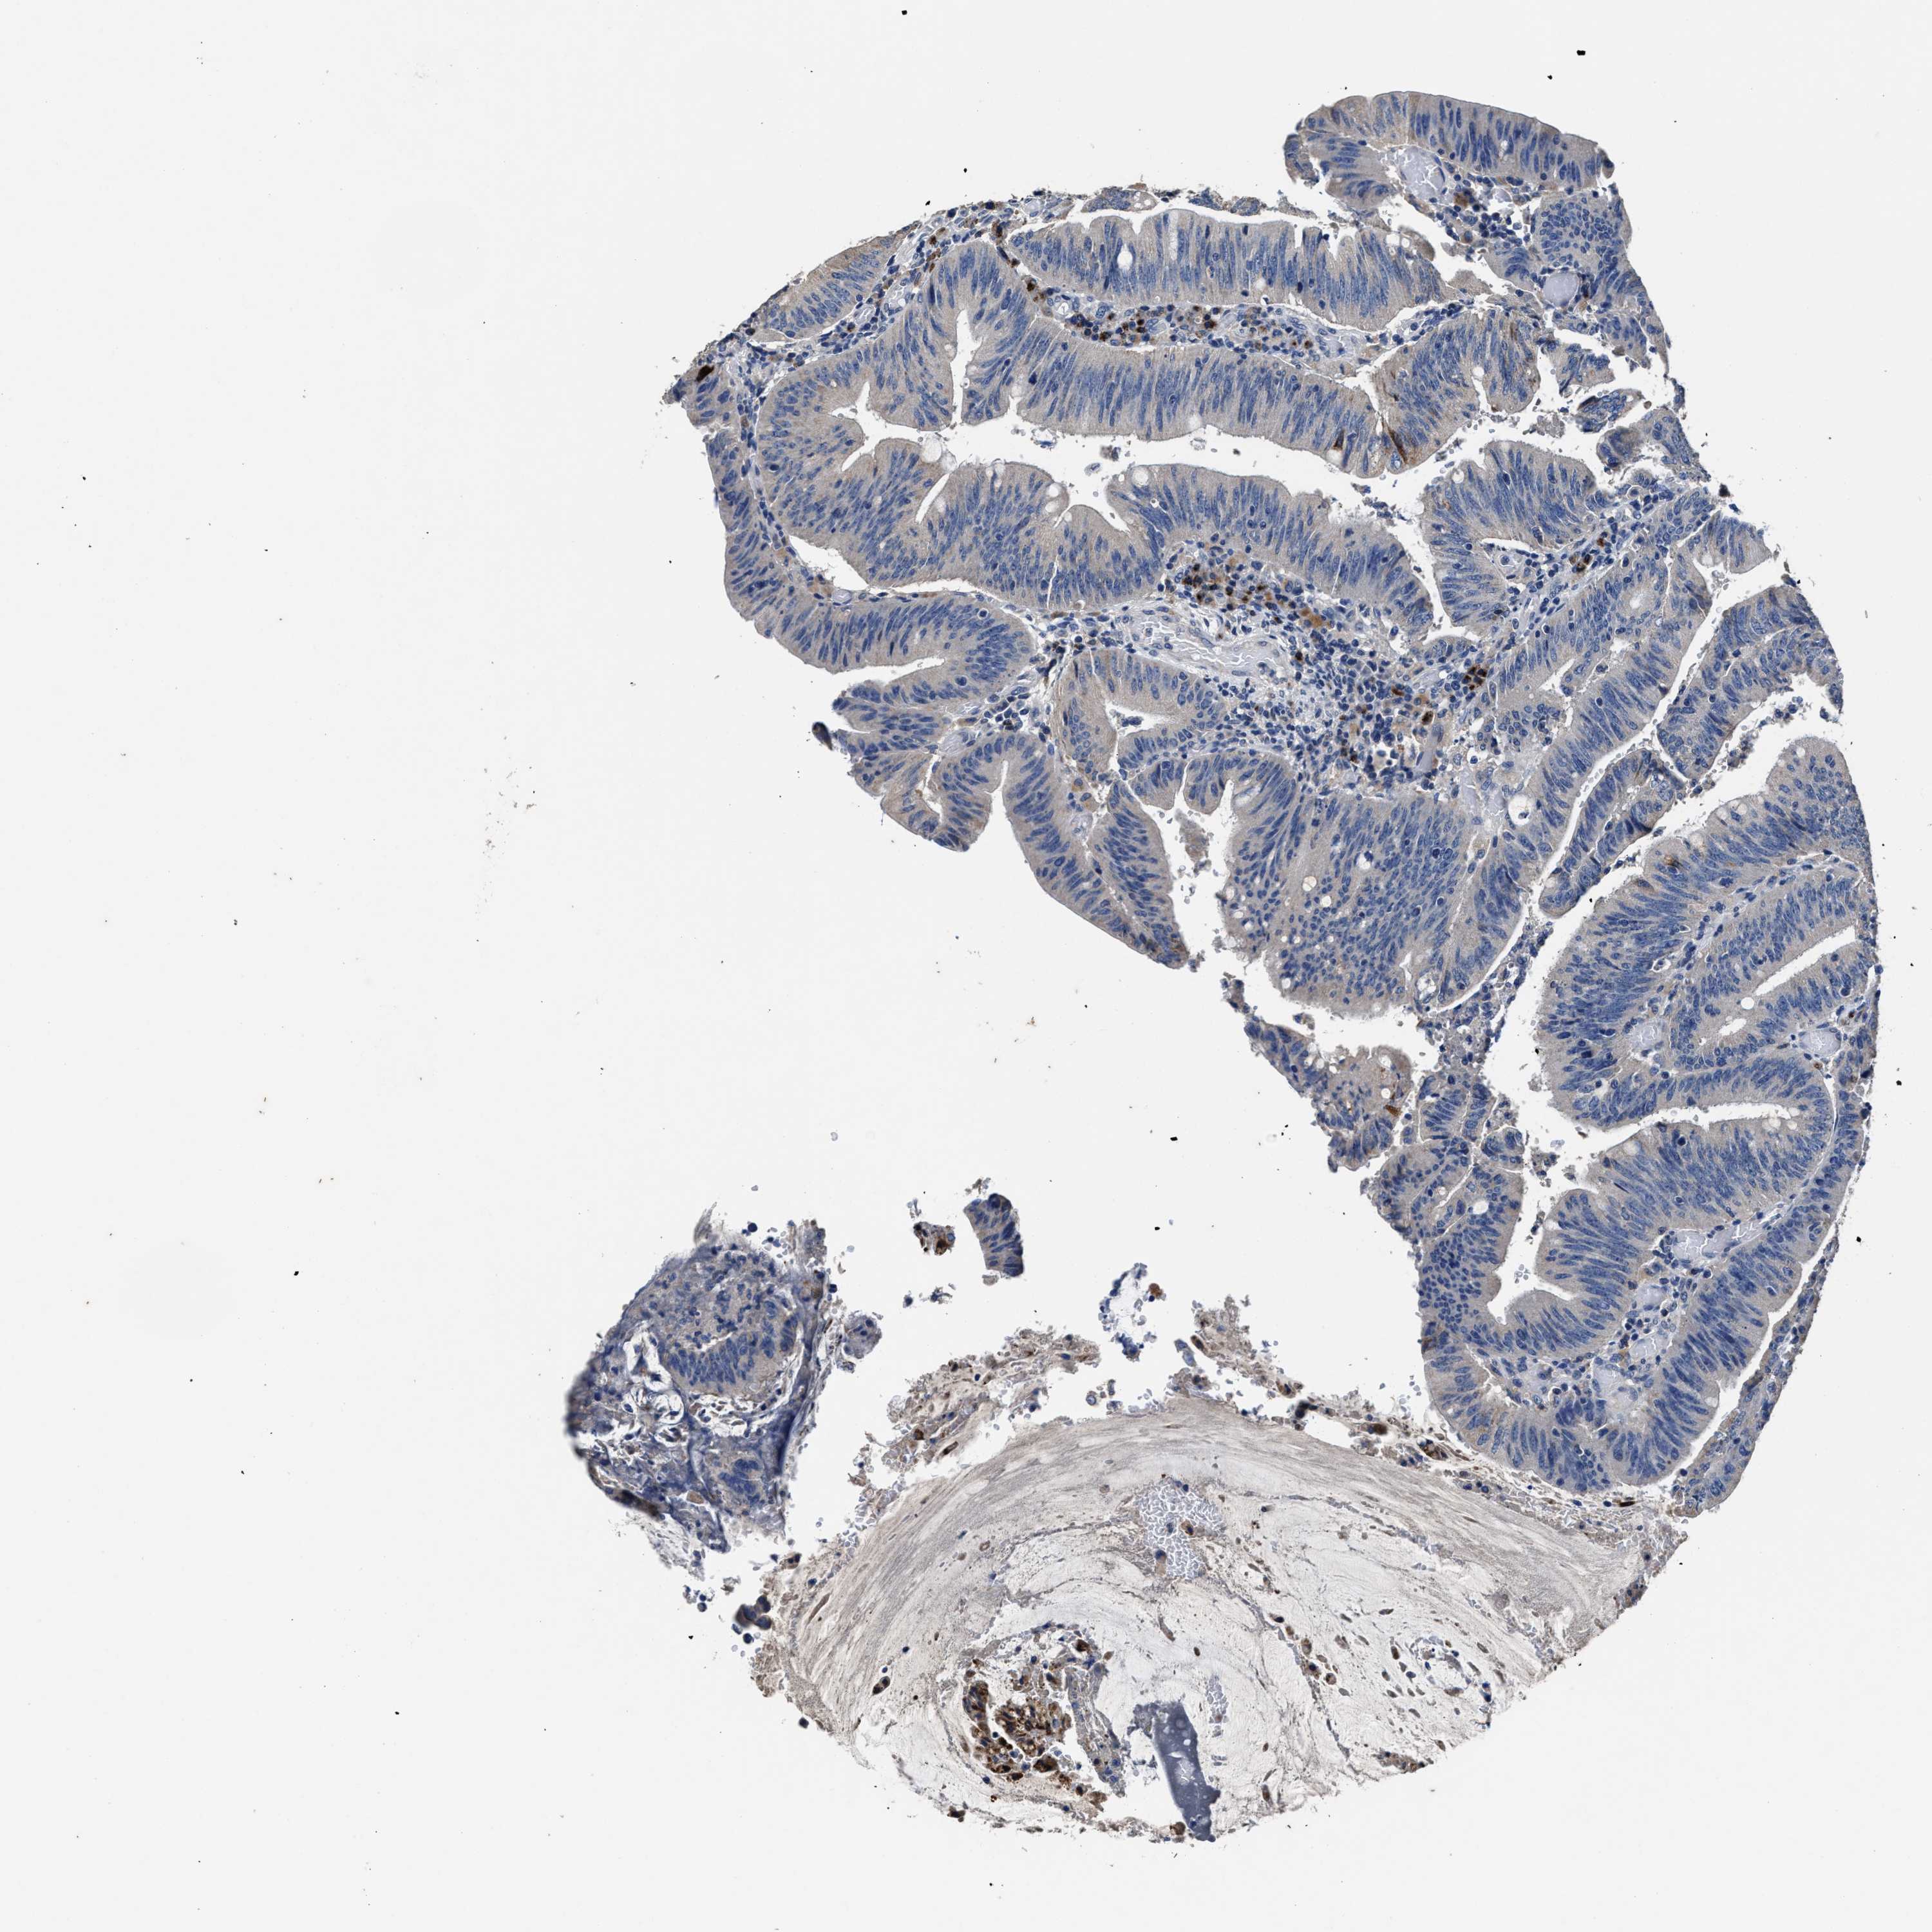

CANCER COLORECTAL CANCER Show tissue menu

ANTIBODIES

AND

VALIDATION